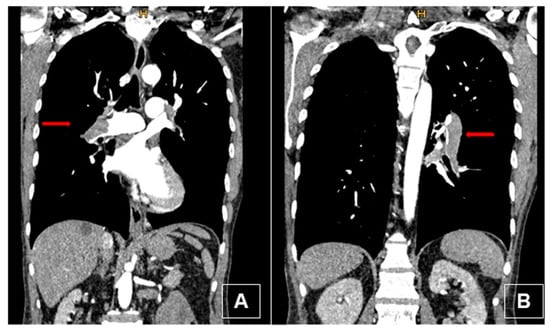

3.4. Computed Tomography Pulmonary Angiography (CTPA)